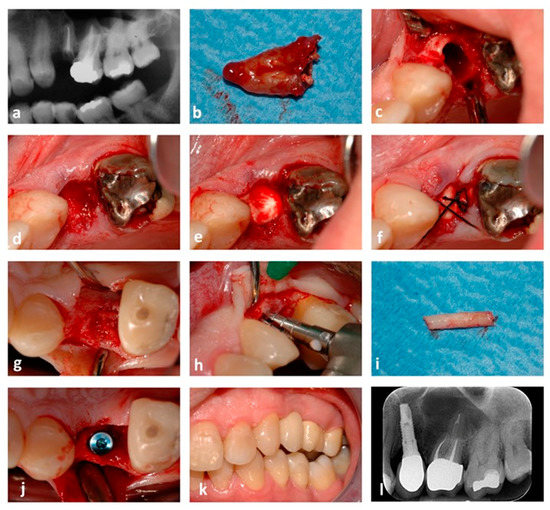

2.4. Surgical Procedure